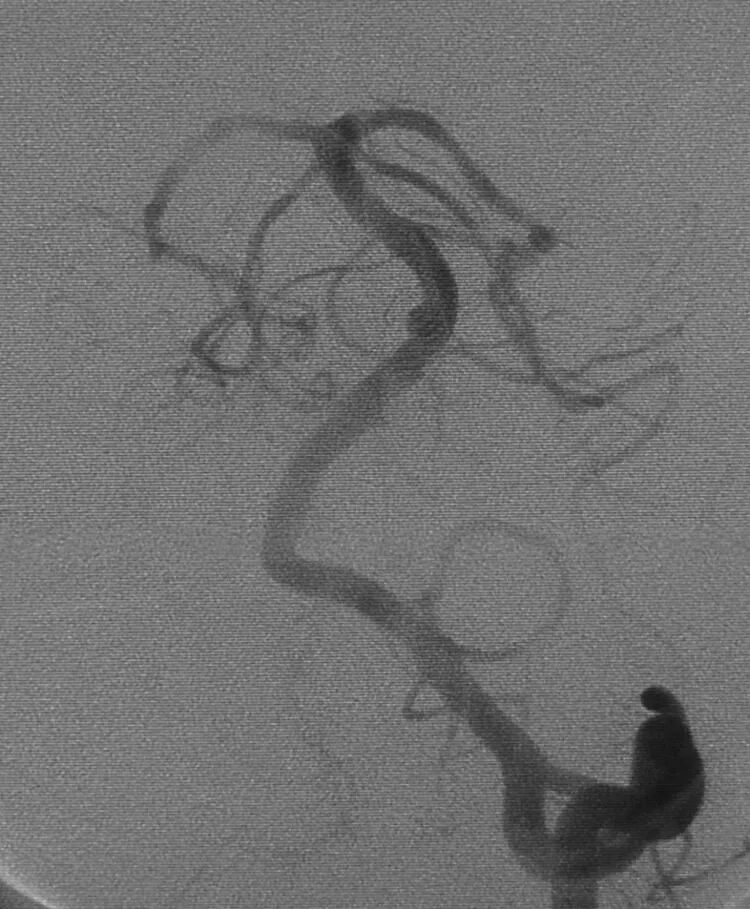

栓塞后的工作位造影和蒙片